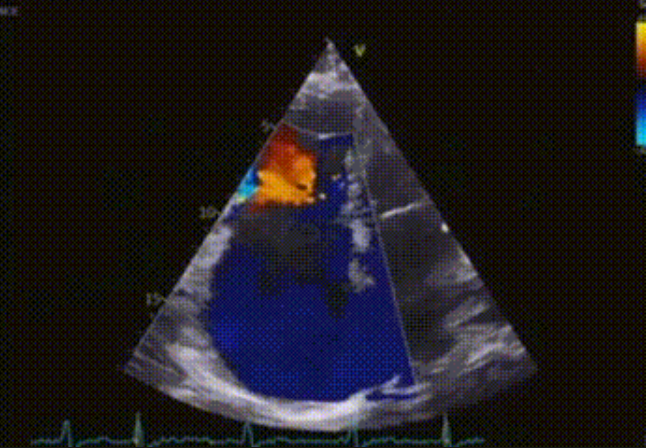

術(shù)前心臟超聲提示:極重度三尖瓣返流,右房容積明顯增大,三尖瓣瓣環(huán)顯著擴(kuò)張。

術(shù)后心臟超聲提示:LuX-Valve Plus植入后,三尖瓣瓣環(huán)處可見(jiàn)人工瓣膜回聲,未見(jiàn)返流,人工瓣膜穩(wěn)定,瓣葉開(kāi)閉良好,連續(xù)多普勒估測(cè)三尖瓣平均跨瓣壓差僅為1mmHg。